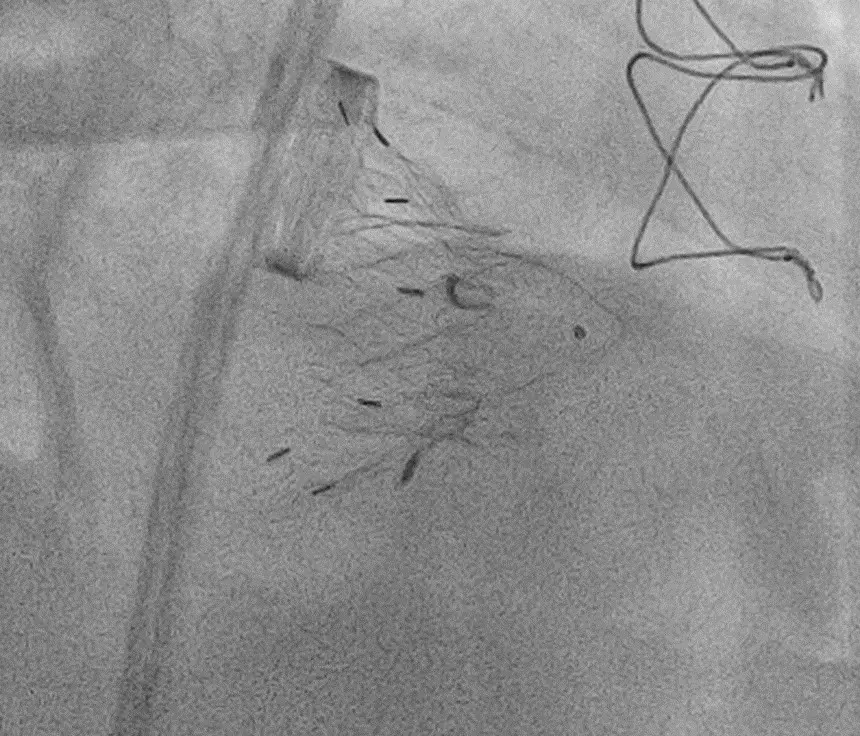

Данные жалобы беспокоят пациента в течении последних 6 месяцев. Учитывая тяжёлую трикуспидальную недостаточность за счёт эктазии кольца трикуспидального клапана, значимую сепарацию (расхождение) створок трикуспидального клапана, препятствующую выполнению пластики по типу «край в край», а также прогрессирование явлений сердечной недостаточности, бесперспективность медикаментозной терапии пациенту была выполнена транскатетерная имплантация трикуспидального клапана.

Применена транскатетерная система замены трёхстворчатого клапана второго поколения. Она предназначена для пациентов с тяжёлой регургитацией трёхстворчатого клапана и высоким хирургическим риском. Система позволяет функционально заменить собственный клапан пациента на искусственный клапан-стент без проведения открытой операции на сердце. Имплантация выполняется через яремную вену, что упрощает операцию, сокращает её длительность, размер разрезов и повреждение тканей сердца. Пациенты сохраняют гемодинамическую стабильность в ходе всей операции, так как отсутствует необходимость искусственного кровообращения. Для контроля имплантации клапана используется чреспищеводная и трансторакальная эхокардиография, рентгеновское исследование не обязательно.

Операция прошла успешна, клапан имплантирован с минимальными парапротезными регургитациями до 1 степени, которые, как правило, закрываются через 1- 3 месяца после имплантации. В настоящее время пациент экстубирован, гемодинамически стабилен и готовится к переводу в отделение для дальнейшей активизации и лечения. (Лечащие врачи Комлев А.Е., Кантемирова М.М.).